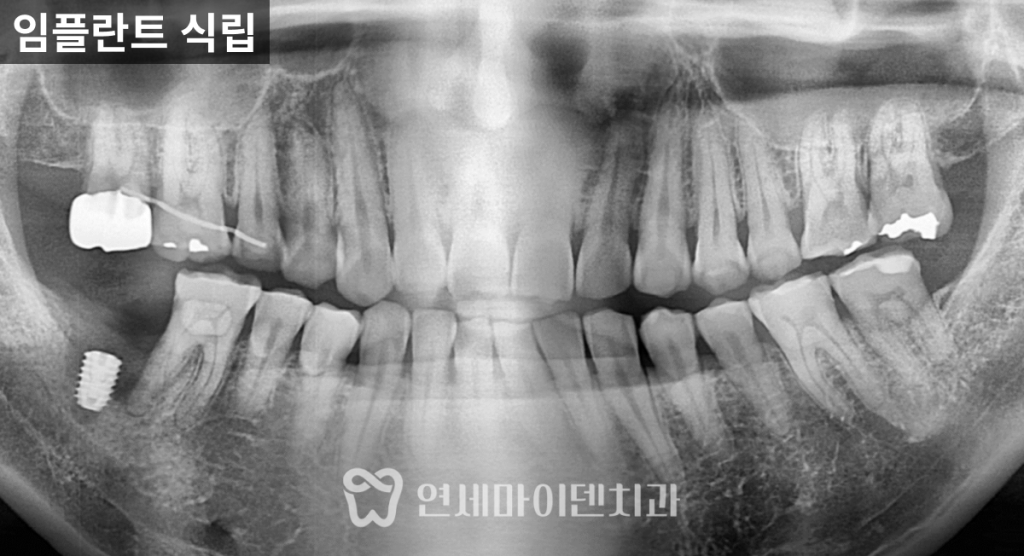

뼈이식과 임플란트 수복 과정

뒤쪽 어금니 부위는

뼈가 절반 이상 소실되어 있었고

혀 쪽 일부 뼈만 남아 있는

난이도 높은 조건이었습니다

이 부위를 기준으로

임플란트 식립과 동시에 뼈이식을 진행하여

앞쪽 자연치가 받는 지지력까지

함께 회복하는 방향으로 치료했습니다.임플란트 위치와 깊이는

하치조 신경관과의 거리,

남아 있는 뼈 상태를 고려해

정밀하게 조정했습니다.

그 결과,

수술 후 X-ray에서 뼈 높이가 뚜렷하게 상승했고

앞쪽 어금니의 흔들림도 눈에 띄게 줄어들었습니다.3년 경과 후 결과